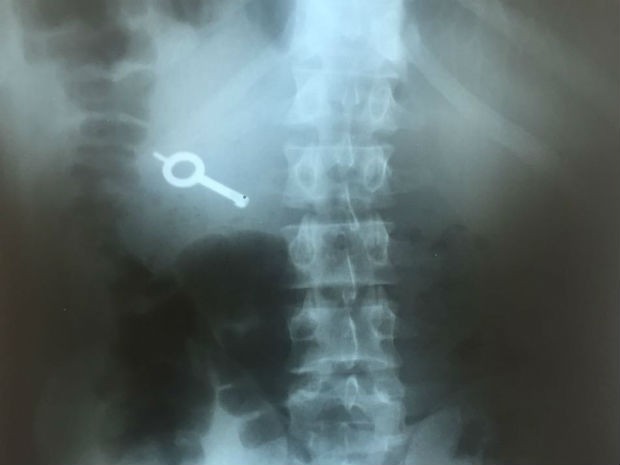

Ainda de acordo com o site, um dos detentos engoliu a chave e foi encaminhado ao Hospital Municipal, onde fez um raio-X que confirmou a ingestão da chave. Ele deve permanecer internado no local até expelir o objeto.